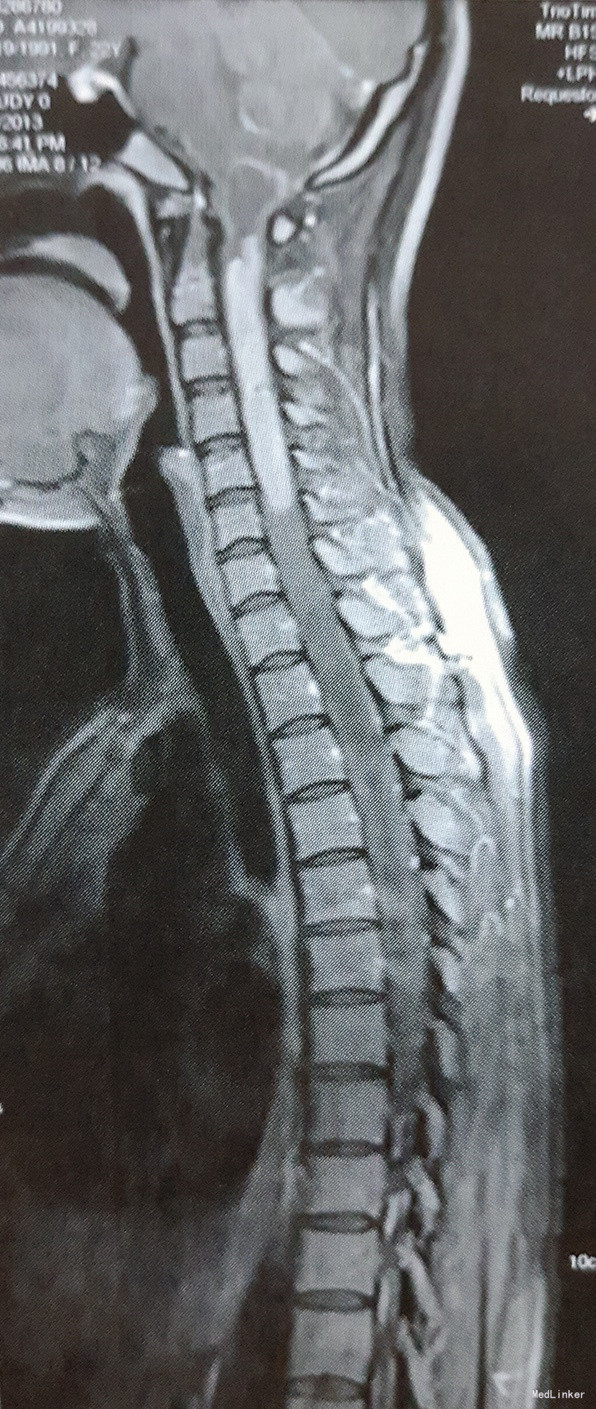

体格检查:左上肢肌力III级,右上肢及双下肢肌力IV级,肌张力降低。左上肢无法上举,右上肢运动正常。左上肢肘关节至肢端浅感觉消失,肘关节以上浅感觉减退;右上肢浅感觉减退,双下肢及躯干深浅感觉未见明显异常。心肺腹体检无明显异常。 影像学:全脊髓MRI结果:延髓-C5椎体平面颈髓稍增粗,可见等T1,等长T2信号,增强扫描均匀强化,下方脊髓可见囊性长T1,长T2信号,下方病灶延伸至T8平面,T9-L1平面脊髓T2信号增高,无明显强化。考虑:1、延髓-C5椎体平面髓内囊实行占位性病变,强化明显,考虑星形细胞瘤可能性大;2、其下方至T8椎体平面脊髓空洞形成。3、T8-L1椎体平面脊髓变性。